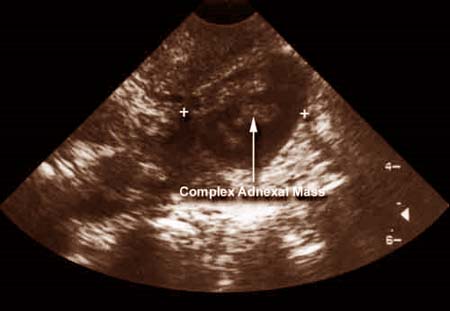

Nhân trường hợp khối sán lá gan lớn giả trang như một ung thư buồng trứng

Bài báo cáo trên do nhóm tác giả Gurkan Yazici, Umut Talat Dilek, Tuba Karabacak, Devrim Ertunc, Metin Korkmaz, Saffet Dilek thuộc khoa sản phụ, đại học y khoa, đại học Mersin, Liparis Plaza, Orkide Blok, Kat: 5, Daire:12, 33170 Mezitli, Mersin, Thổ Nhĩ Kỳ công bố trên tạp chí ung thư phụ khoa Gynecol oncol. 2005 Oct ;99 (1):236-8 16051339. Với một chẩn đoán trước sinh/trước mổ là một ung thư buồng trứng vẫn còn là một vấn đề do đa bệnh khi xuất hiện ở vùng chậu một khối u. Bệnh sán lá gan lớn là một bệnh ký sinh trùng gây triệu chứng lâm sàng độc nhất. Bệnh nhân là một phụ nữ 49 tuổi nhập viện với phàn nàn là thỉnh thoảng có cơn đau bụng. Khám vùng chậu cho thấy có một khối dính bên (P). Xét nghiệm chất chỉ điểm khối u CA-125 huyết thanh cho thấy tăng. Mổ bụng thăm dò được thực hiện với một chẩn đoán ban đầu là khối u buồng trứng, song chẩn đoán cuối cùng là khối abces do sán lá gan lớn dính thân (adnexal fascioliasis).

Điều này, đặt ra một hướng chẩn đoán mới khi gặp khối u vùng chậu, làm thế nào lý giải có sự tăng nồng độ CA-125, trong khi ung thư buồng trứng là một chẩn đoán phân biệt đầu tiên, triệu chứng lâm sàng không điển hình của sán lá gan lớn, có thể đưa người thầy thuốc vào một chẩn đoán nhầm là u ác tính.